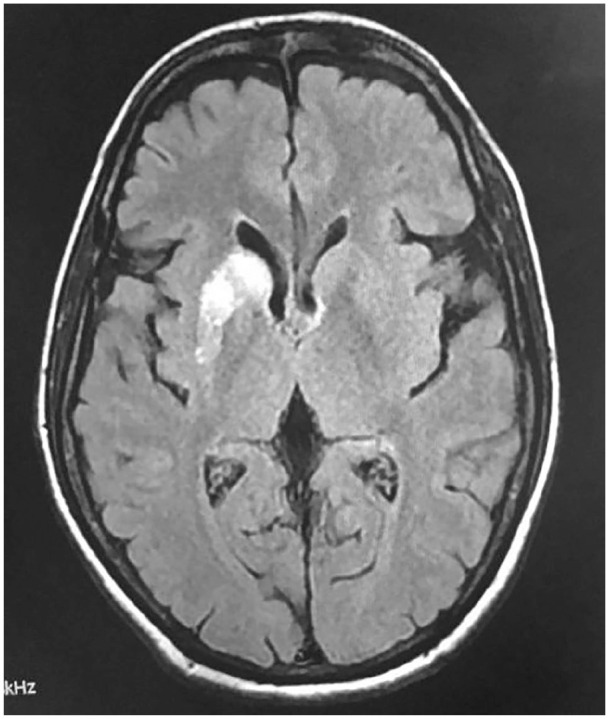

Chorea Hyperglycemia Basal Ganglia Syndrome (CHBG) is an uncommon neurological complication arising in diabetic patients with severe, non-ketotic hyperglycemia. This case report describes a 50-year-old woman presenting with new-onset, choreiform movements in her extremities. Initial workup revealed uncontrolled diabetes (plasma glucose 410 mg/dl, HbA1c 11.2%) with negative serum ketones. Brain MRI findings supported the diagnosis, demonstrating characteristic T1 hyperintensity in the right basal ganglia. Implementation of gradual glycemic control over 48 hours led to significant improvement of her symptoms. This case emphasizes the importance of considering CHBG in the differential diagnosis of movement disorders in patients with uncontrolled diabetes. Early recognition and prompt glycemic management can lead to complete resolution of symptoms, highlighting the crucial role of maintaining proper blood sugar control in diabetic patients.